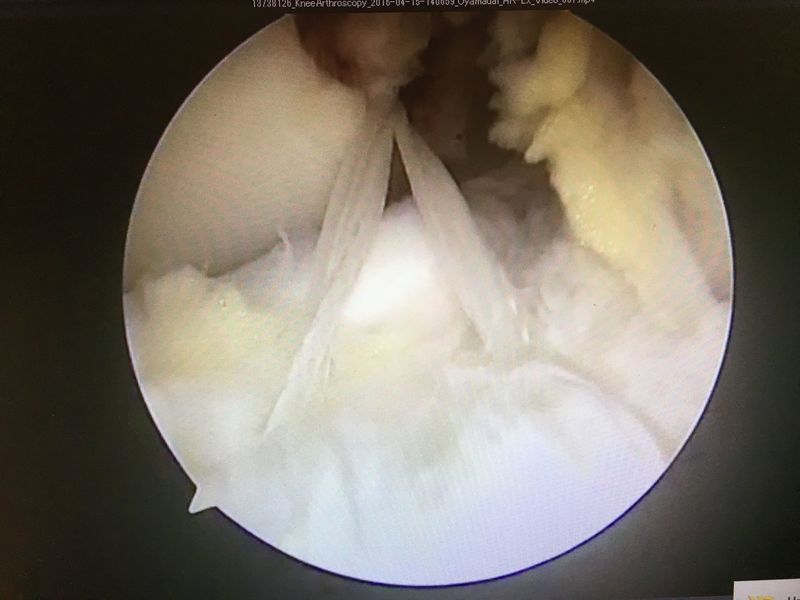

![]() | ![]() | ![]() |

| ACLは緊張がなく機能していない | 外側半月板は問題なし | 内側半月板は問題なし |

ACL再建

| 大腿骨孔作成 | グラフト挿入 | 再建靭帯 |